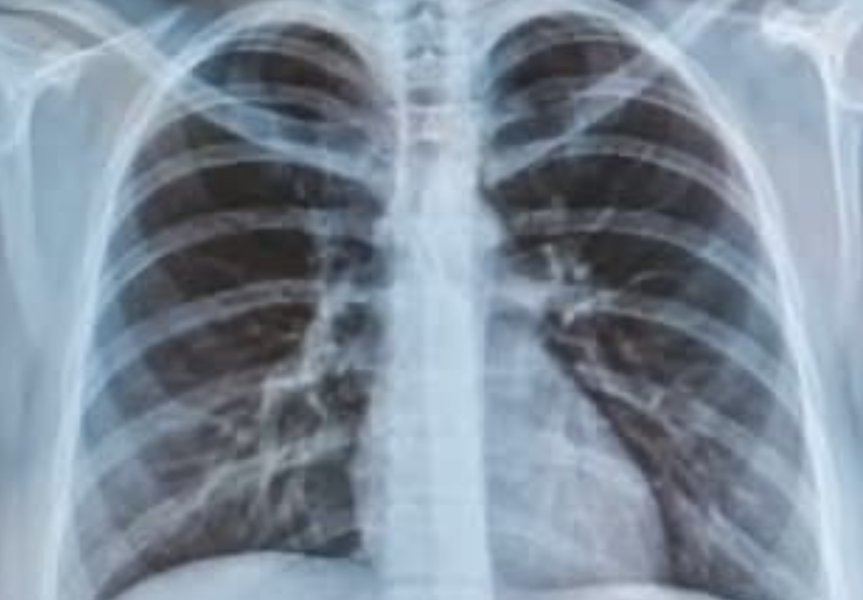

Associate Professor Atikun Limsukon, a respiratory and critical care physician at Chiang Mai University, said the case was diagnosed as acute eosinophilic pneumonia, a condition that can occur in healthy non-smokers exposed to heavy smoke or airborne toxins.

A second patient with a chronic lung condition returned in respiratory failure and required intubation, with doctors reporting severe inflammation and blood-stained fluid in the lungs — signs of significantly worsened damage.